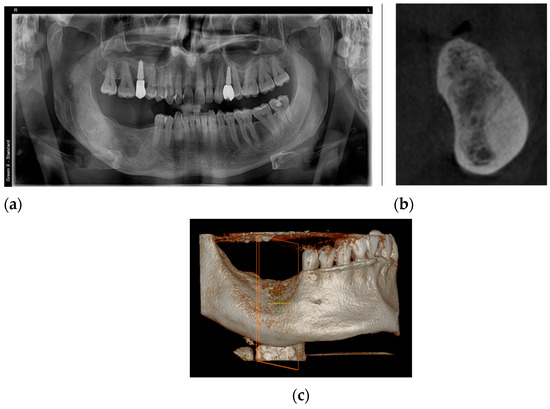

2. Case Presentation